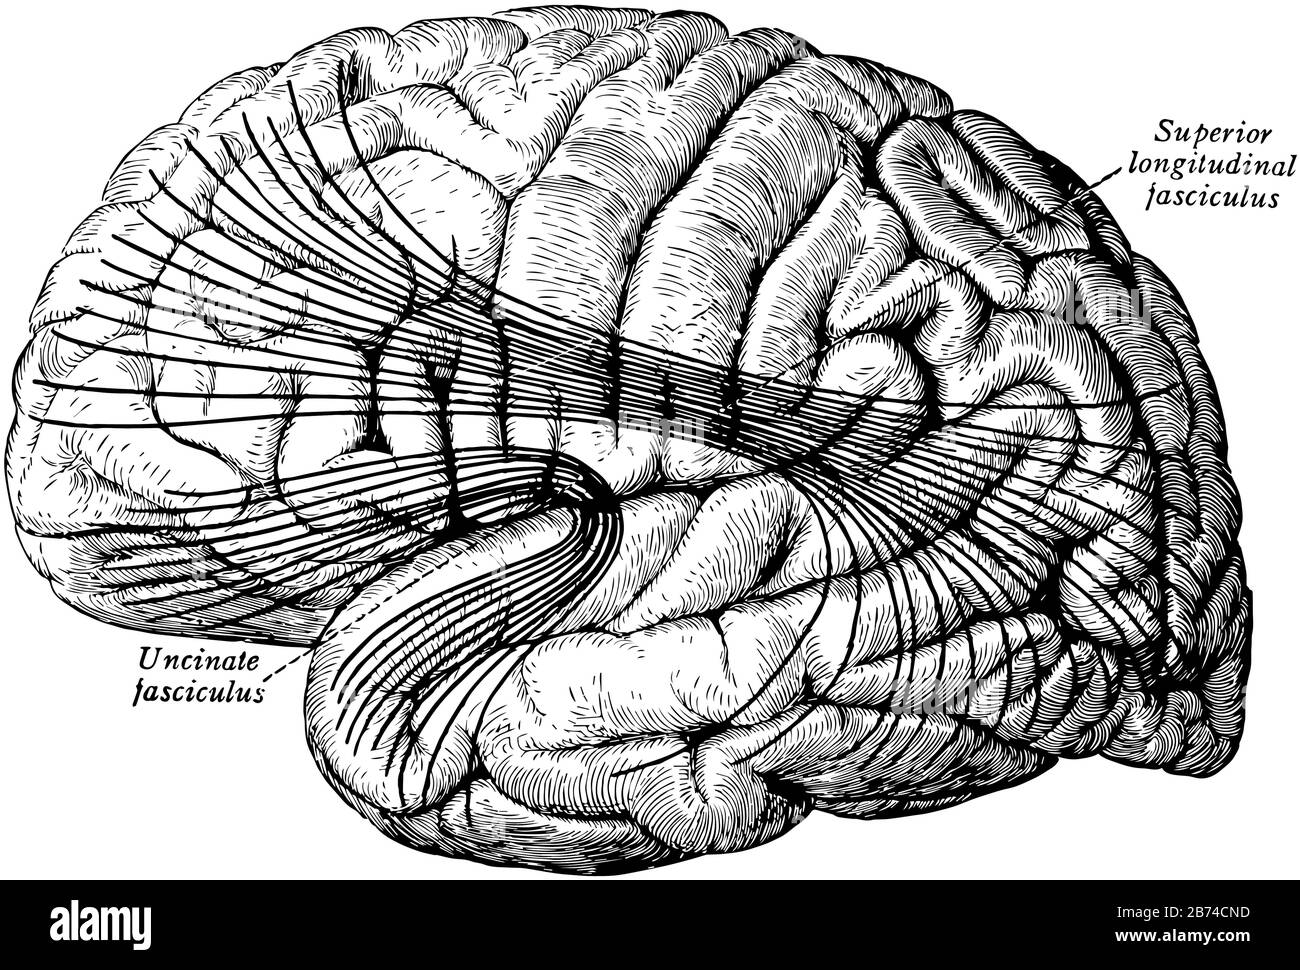

RF2BTH97P–Una rappresentazione tipica della corteccia cerebrale, i tratti di associazione più importanti del cervello. Le fibre sono proiettate sul mesiale (mediale)

RF2B74CND–I tratti di associazione più importanti del cervello, disegno di linea vintage o illustrazione di incisione.